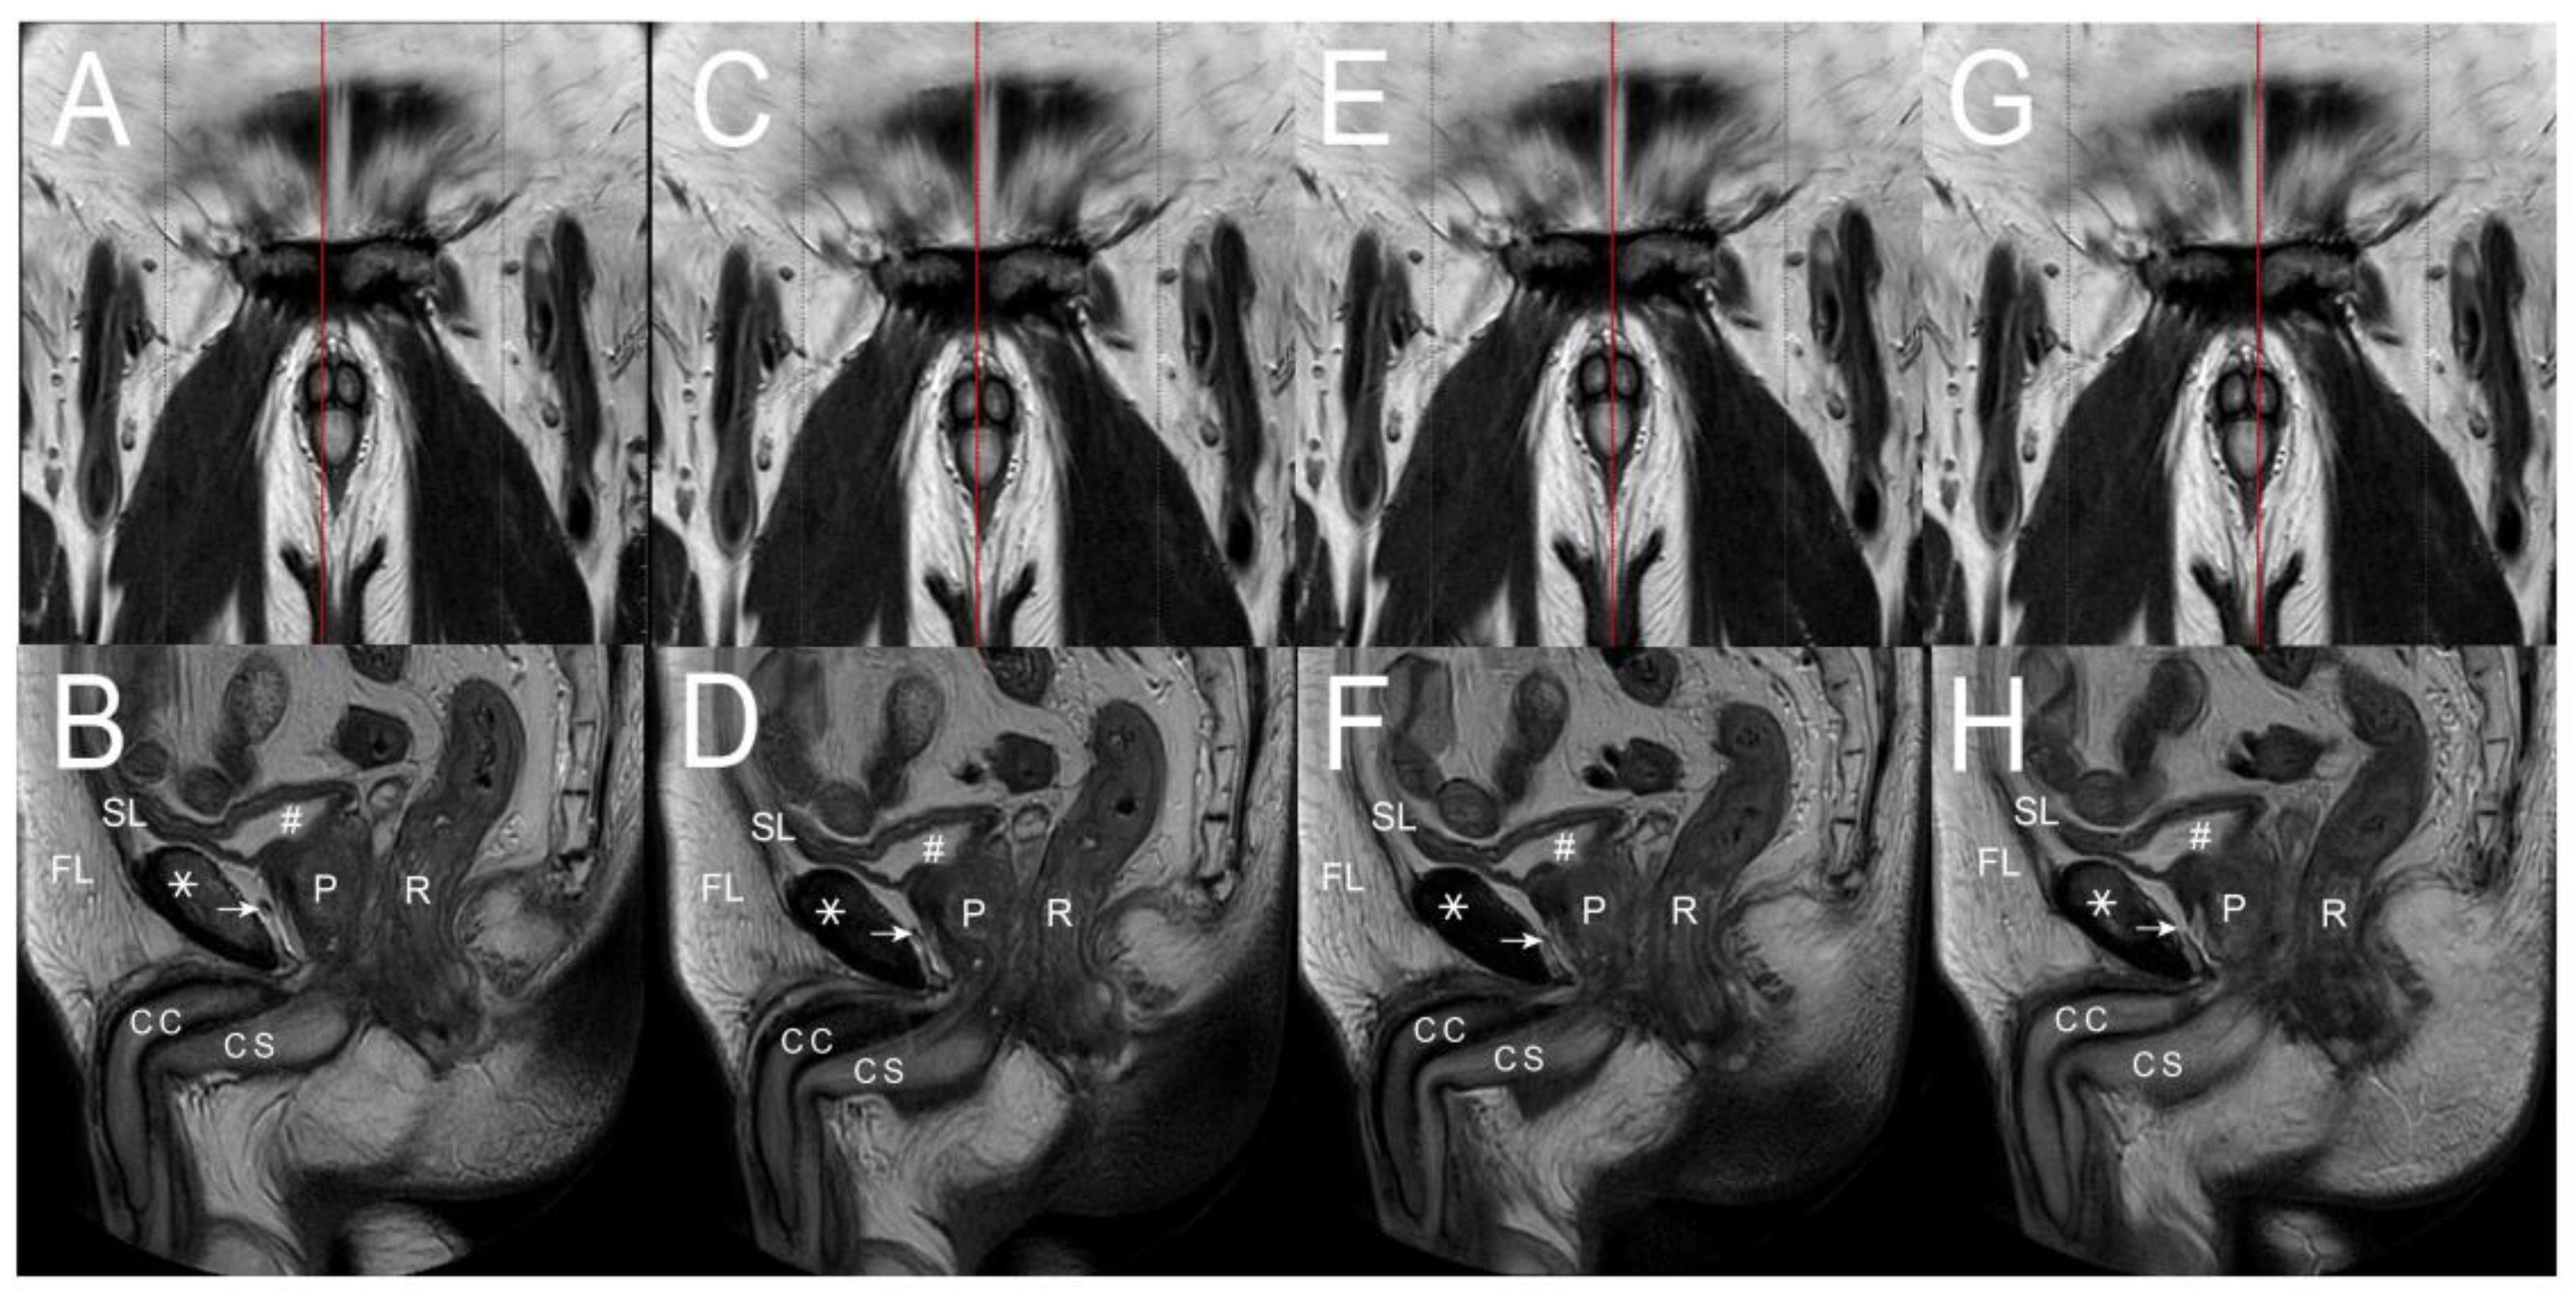

- Hsu, G.L.; Hill, J.W.; Chen, H.S.; Huang, S.-J. Novel pilot films providing indispensable information in pharmaco-cavernosography. Transl. Androl. Urol. 2014, 4, 398–405. [Google Scholar]

- Ghafoori, M. CT Cavernosography: A New Method for Evaluating venous Incompetence in Impotent Patients. Indian J. Radiol. 2010, 7, e78769. [Google Scholar]

- Kurbatov, D.G.; Kuznetsky, Y.Y.; Kitaev, S.V.; Brusensky, V.A. Magnetic resonance imaging as a potential tool for objective visualization of venous leakage in patients with veno-occlusive erectile dysfunction. Int. J. Impot. Res. 2008, 20, 192–198. [Google Scholar] [CrossRef] [PubMed][Green Version]